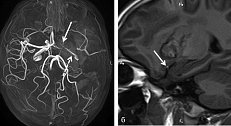

Самый практичный «переключатель» — локализация и предполагаемый механизм кровоизлияния, но одной дихотомии «лобарное/нелобарное» часто недостаточно: дополнительную роль играют МРТ-маркеры высокого риска, особенно при подозрении на церебральную амилоидную ангиопатию (например, кортикальная поверхностная сидероз, convexity SAH, высокая нагрузка микрокровоизлияний).

Лобарное ВМК — кровоизлияние в долях больших полушарий, ближе к коре. Оно чаще ассоциируется с церебральной амилоидной ангиопатией и, в среднем, с более высоким риском рецидива, особенно при наличии неблагоприятных МРТ-маркеров.

Нелобарное, глубинное ВМК — базальные ганглии, таламус, ствол, мозжечок. Чаще связано с гипертензивным поражением мелких артерий; при жестком контроле артериального давления профиль рецидива может быть другим.

Если у пациента есть МРТ-признаки высокого риска повторных кровоизлияний, решение об антикоагуляции требует значительно большей осторожности и чаще смещается в сторону обсуждения альтернатив.